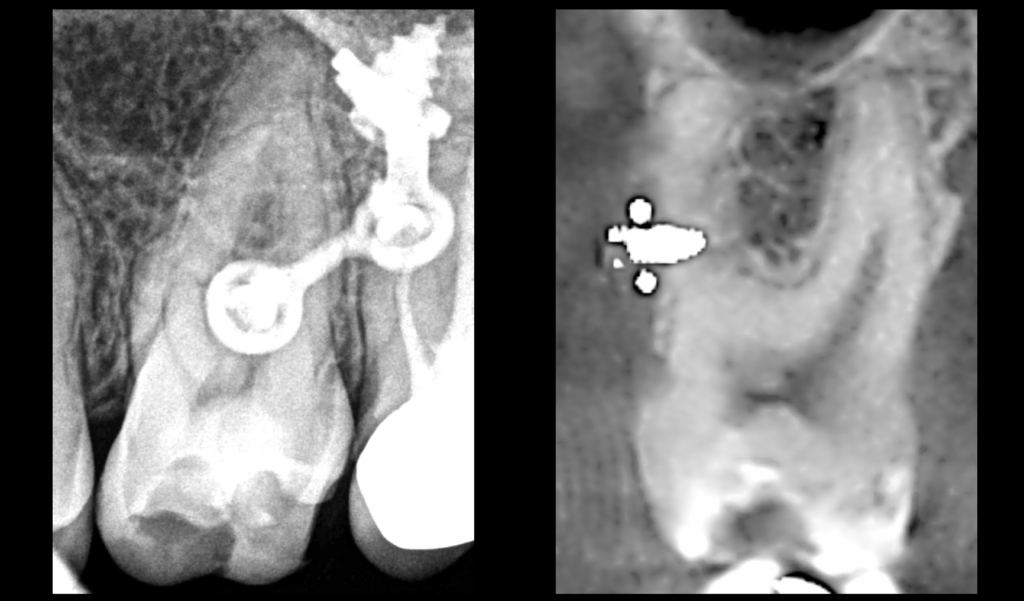

🔍 𝐍𝐨𝐭𝐫𝐞 𝐩𝐚𝐭𝐢𝐞𝐧𝐭 𝐞𝐬𝐭 𝐞𝐧 𝐩𝐮𝐥𝐩𝐢𝐭𝐞 𝐚𝐢𝐠𝐮̈𝐞 𝐢𝐫𝐫𝐞́𝐯𝐞𝐫𝐬𝐢𝐛𝐥𝐞 𝐬𝐮𝐫 𝐬𝐚 𝐝𝐞𝐧𝐭 𝐧°26 : 𝐩𝐨𝐮𝐫𝐪𝐮𝐨𝐢 ❓

➡️ Réponse : parce qu’une vis d’ostéosynthèse a été mise en place en plein milieu de la racine MV